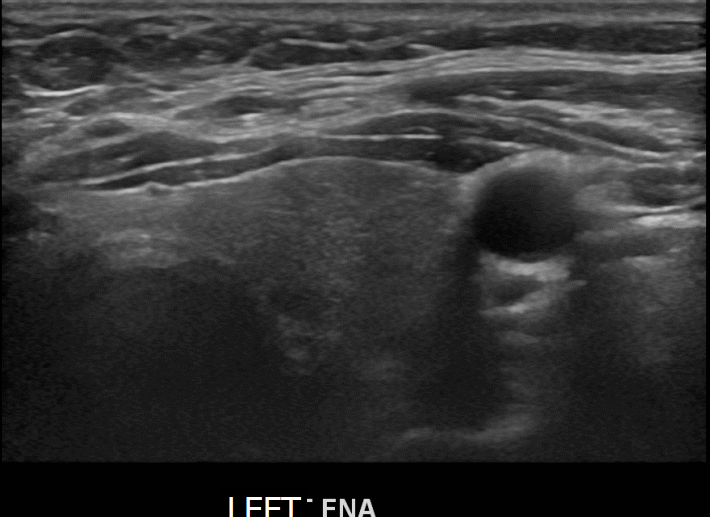

상기환자 검진이상으로  내원하신 50대중반 여성분으로 의심스러운 좌엽혹 세포검사진행후 갑상선암으로 진단되었습니다